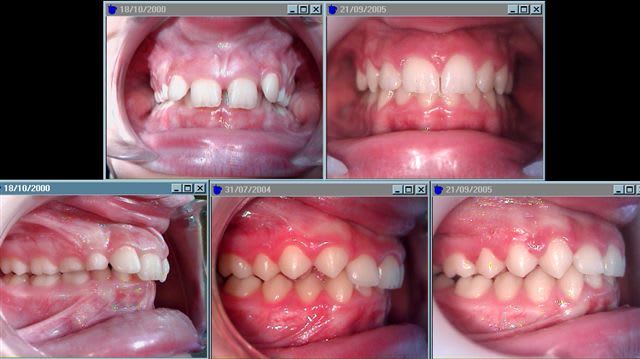

Un autre exemple : Jeune fille de 9 ans et demi. traitement commencé en janvier, revue hier. Uniquement en activateur.

Exemple supra sb vafkci - Eugenol